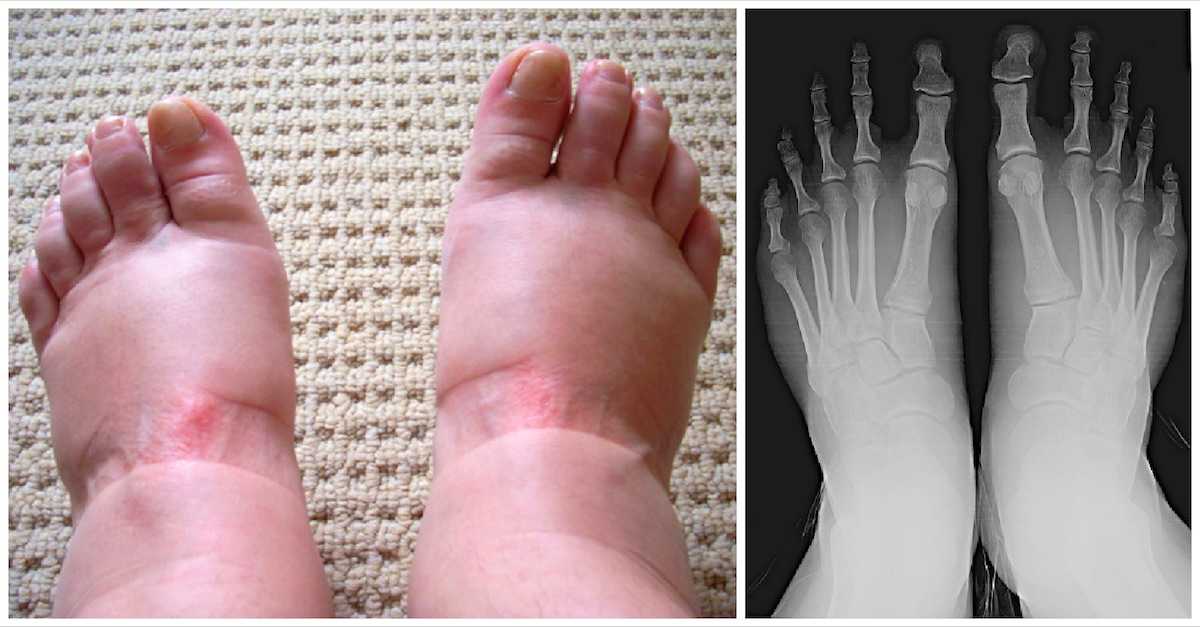

My feet are swollen-29/1/ Exercising regularly and maintaining a healthy weight can reduce the risk of swollen feet Other ways to alleviate swollen feet include drinking plenty ofWhat Causes Swollen Feet There are many factors and conditions that can cause swelling in the legs and/or feet, including Prolonged periods of sitting or standing, often made worse in heat Overweight/obesity Chronic venous insufficiency, caused by faulty valves in the veins of the legs Cardiovascular and/or respiratory diseases

26/6/ Sometimes swollen feet have causes that are not directly related to the flow of body fluids For example Bone and tendon conditions Several problems with the bones and tendons in your feet also can cause swelling, although (in contrast to the vascular causes) they also typically cause pain Examples include fractures, arthritis, and tendinitis14/5/21 Causes of Swollen Feet Swollen feet may happen due to many reasons some of them are ignorable as they get disappear by own and some of them needs immediate medical attention otherwise it can cause a major health concern Below we have mentioned most common causes of the swollen feet, ankle, and legs along with its treatment methodIf you are prone to having swelling on your feet and legs, then do the following Every 30 minutes, get up from your seat and walk around Early in the morning, lie down on the floor (on a mat), and prop up both your legs on a chair by your feet Stretch out both hands, with palms up

Common causes of swollen ankles, feet and legs Swelling in the ankles, feet and legs is often caused by a buildup of fluid in these areas, called oedema Oedema is usually caused by standing or sitting in the same position for too long eating too much salty food being overweight10/5/18 Painless swelling of the feet or ankles is common and can happen for a variety of reasons Causes of swollen feet can include staying onTo determine the cause of your swollen feet, your doctor will ask you to describe your symptoms and provide a detailed medical history He or she will be able to tell a lot about your swollen feet just by looking at them

Very painfull to walk Swelling, Indegestion and Methadone hammertoe and bunion surgery and swelling SWOLLEN FEET Swelling of hands,feet, and ankles will not go away! Sometimes swollen feet have causes that are not directly related to the flow of body fluids For example Bone and tendon conditions Several problems with the bones and tendons in your feet also can cause swelling, although (in contrast to the vascular causes) they also typically cause pain Examples include fractures, arthritis, and tendinitisHere's a quick look at five reasons why your feet may appear swollen 1